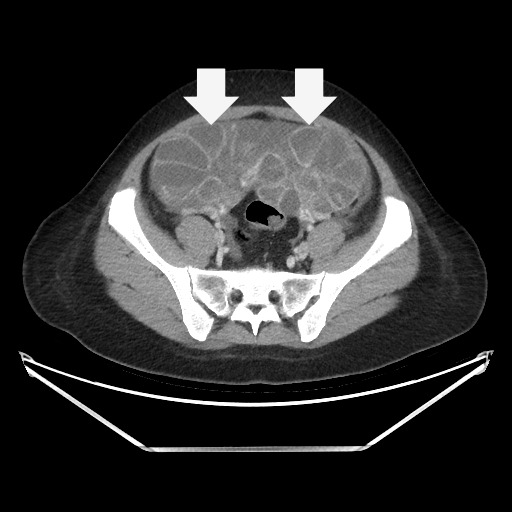

Ovarian hyperstimulation syndrome (OHSS) is a potentially life-threatening complication of assisted reproductive technology (ART). Here, we present the case report of a 30-year-old female undergoing infertility treatment who presented to the emergency department (ED) with nausea and vomiting, abdominal distention, and shortness of breath. On physical exam, she had notable ascites. Computed tomography (CT) of the abdomen and pelvis and pelvic ultrasound (US) revealed significant ascites and enlarged ovaries with multiple cysts. She was diagnosed with severe OHSS and admitted to obstetrics and gynecology (OBGYN) service for five days where she underwent intravenous (IV) hydration and paracentesis. This case report reviews the clinical presentation, categorization, management, and prevention of OHSS and provides examples of imaging findings consistent with the condition.